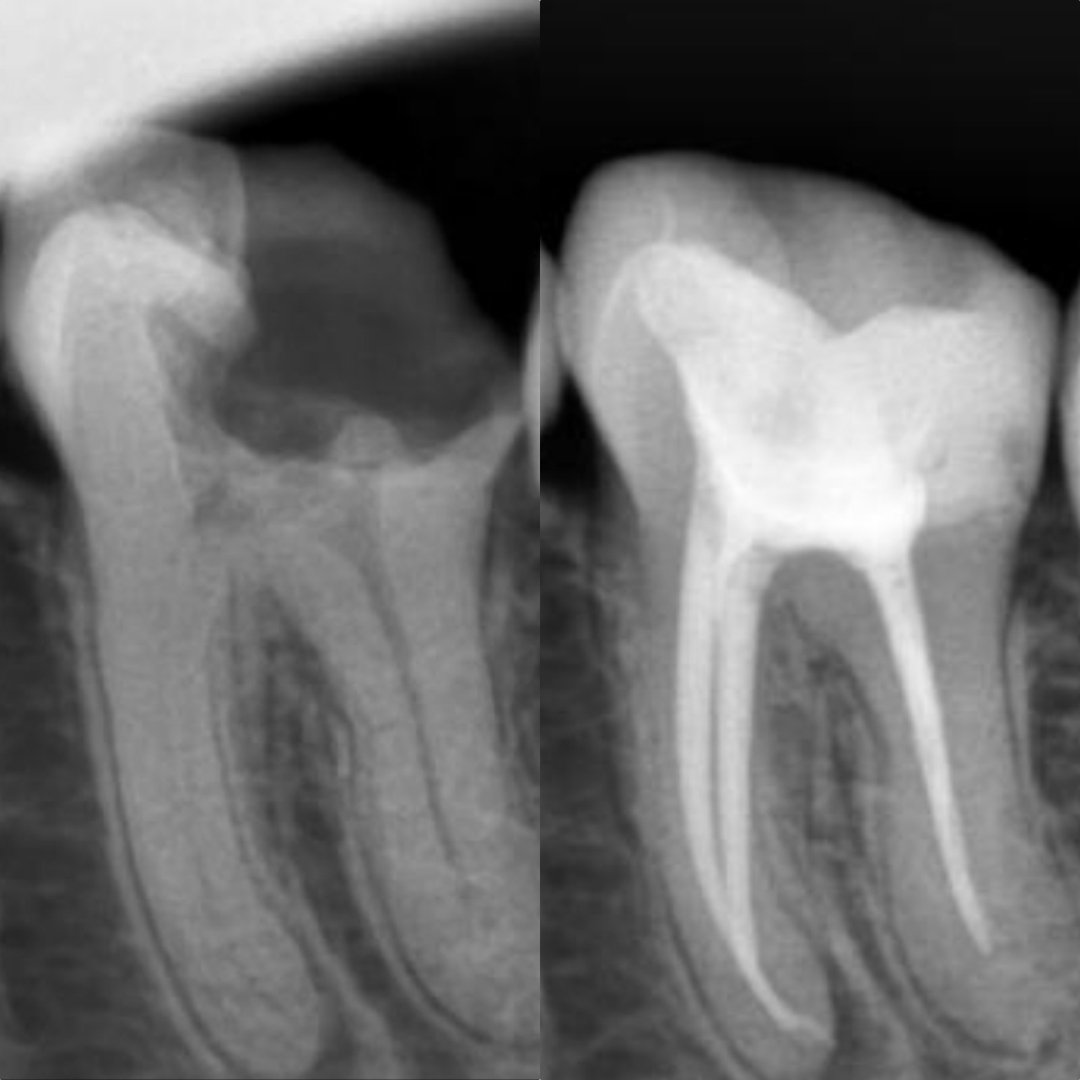

Before After Perawatan Saluran Akar (PSA) di Klinik Utama Pondok Gigi Jakarta

Transformasi nyata setelah perawatan saluran akar (PSA) di Klinik Utama Pondok Gigi Jakarta. Dari gigi rusak dan nyeri hingga kembali sehat dan berfungsi normal. Dikerjakan oleh dokter gigi profesional dengan teknik endodontik modern dan alat berteknologi tinggi untuk hasil maksimal.